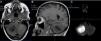

Presentamos el caso de una mujer de 52 años, sin antecedentes de interés, que fue derivada a nuestro centro tras ser diagnosticada de una lesión ocupante de espacio en el hemisferio cerebeloso derecho. La sospecha inicial era de metástasis. En la RMN cerebral, sin embargo, se apreciaba una marcada restricción en la secuencia de difusión concordante con un absceso cerebeloso. La paciente se había sometido a una limpieza dental tres semanas antes. El análisis microbiológico tras la evacuación quirúrgica de la lesión mostró la presencia de Streptococcus intermedius.

A 52-year-old woman with no relevant previous medical history was diagnosticated of an infratentorial bulky cerebellar mass. The mass showed restricted diffusion on MR images, which was consistent with cerebellar abscess. The patient had undergone a minor dental procedure three weeks before. Microbiological analysis after surgical evacuation of the mass confirmed the presence of Streptococcus intermedius.